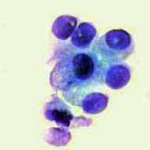

Κατόπιν αυτού, παρακέντηση λεπτής βελόνης κάτω από υπερηχογραφικό έλεγχο και άμεση χρώση παρασκευάσματος κατά Papanicolaou. Κυτταρολογικώς χαρακτηριστικές εικόνες νεοπλασίας.

Η εξέταση μετά από μικρή μερική μαστεκτομή, κατέδειξε λοβικό Ca μαστού με ελεύθερους τους μασχαλιαίους αδένες.